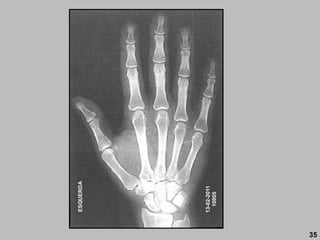

35

DIREITA